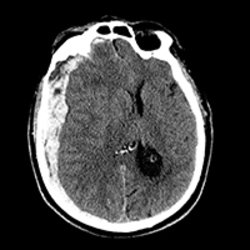

DXAI is a decentralized platform that leverages artificial intelligence to provide advanced diagnostic services for medical imaging and healthcare data. The platform consists of a team of specialized AI agents designed to analyze various medical imaging modalities such as CT scans, X-rays, or MRIs. DXAI operates on a blockchain infrastructure and uses the $DXAI token for transactions within its Diagnostic as a Service (DaaS) model. By integrating domain-specific AI models with decentralized technology, DXAI aims to enhance healthcare accessibility, scalability, and efficiency while maintaining data security and compliance with medical standards.